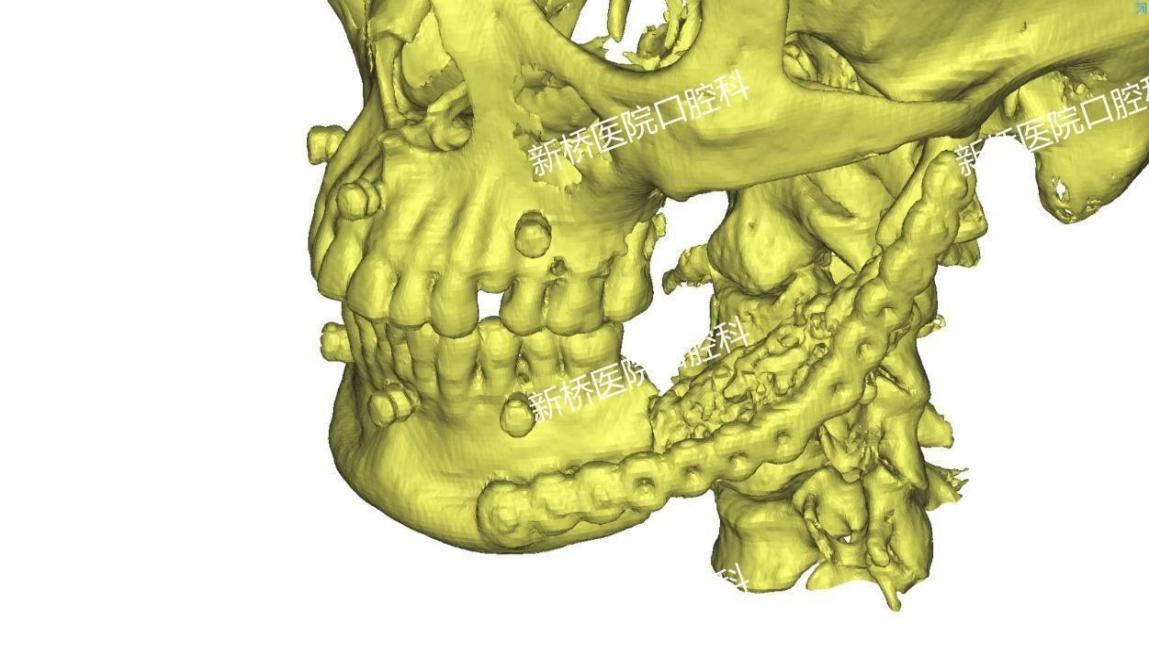

诱导膜技术修复颌骨缺损

多是在骨科当中应用,用于处理骨折、关节病变或骨质疏松等问题。它的主要原理就是在植入之后,能形成一层诱导膜,这层膜内部可以产生成骨微环境,诱导成骨,膜内填入骨松质后就可以在它的诱导下形成新骨。因此骨水泥主要有填充缺损、支撑以及诱导成骨的作用。